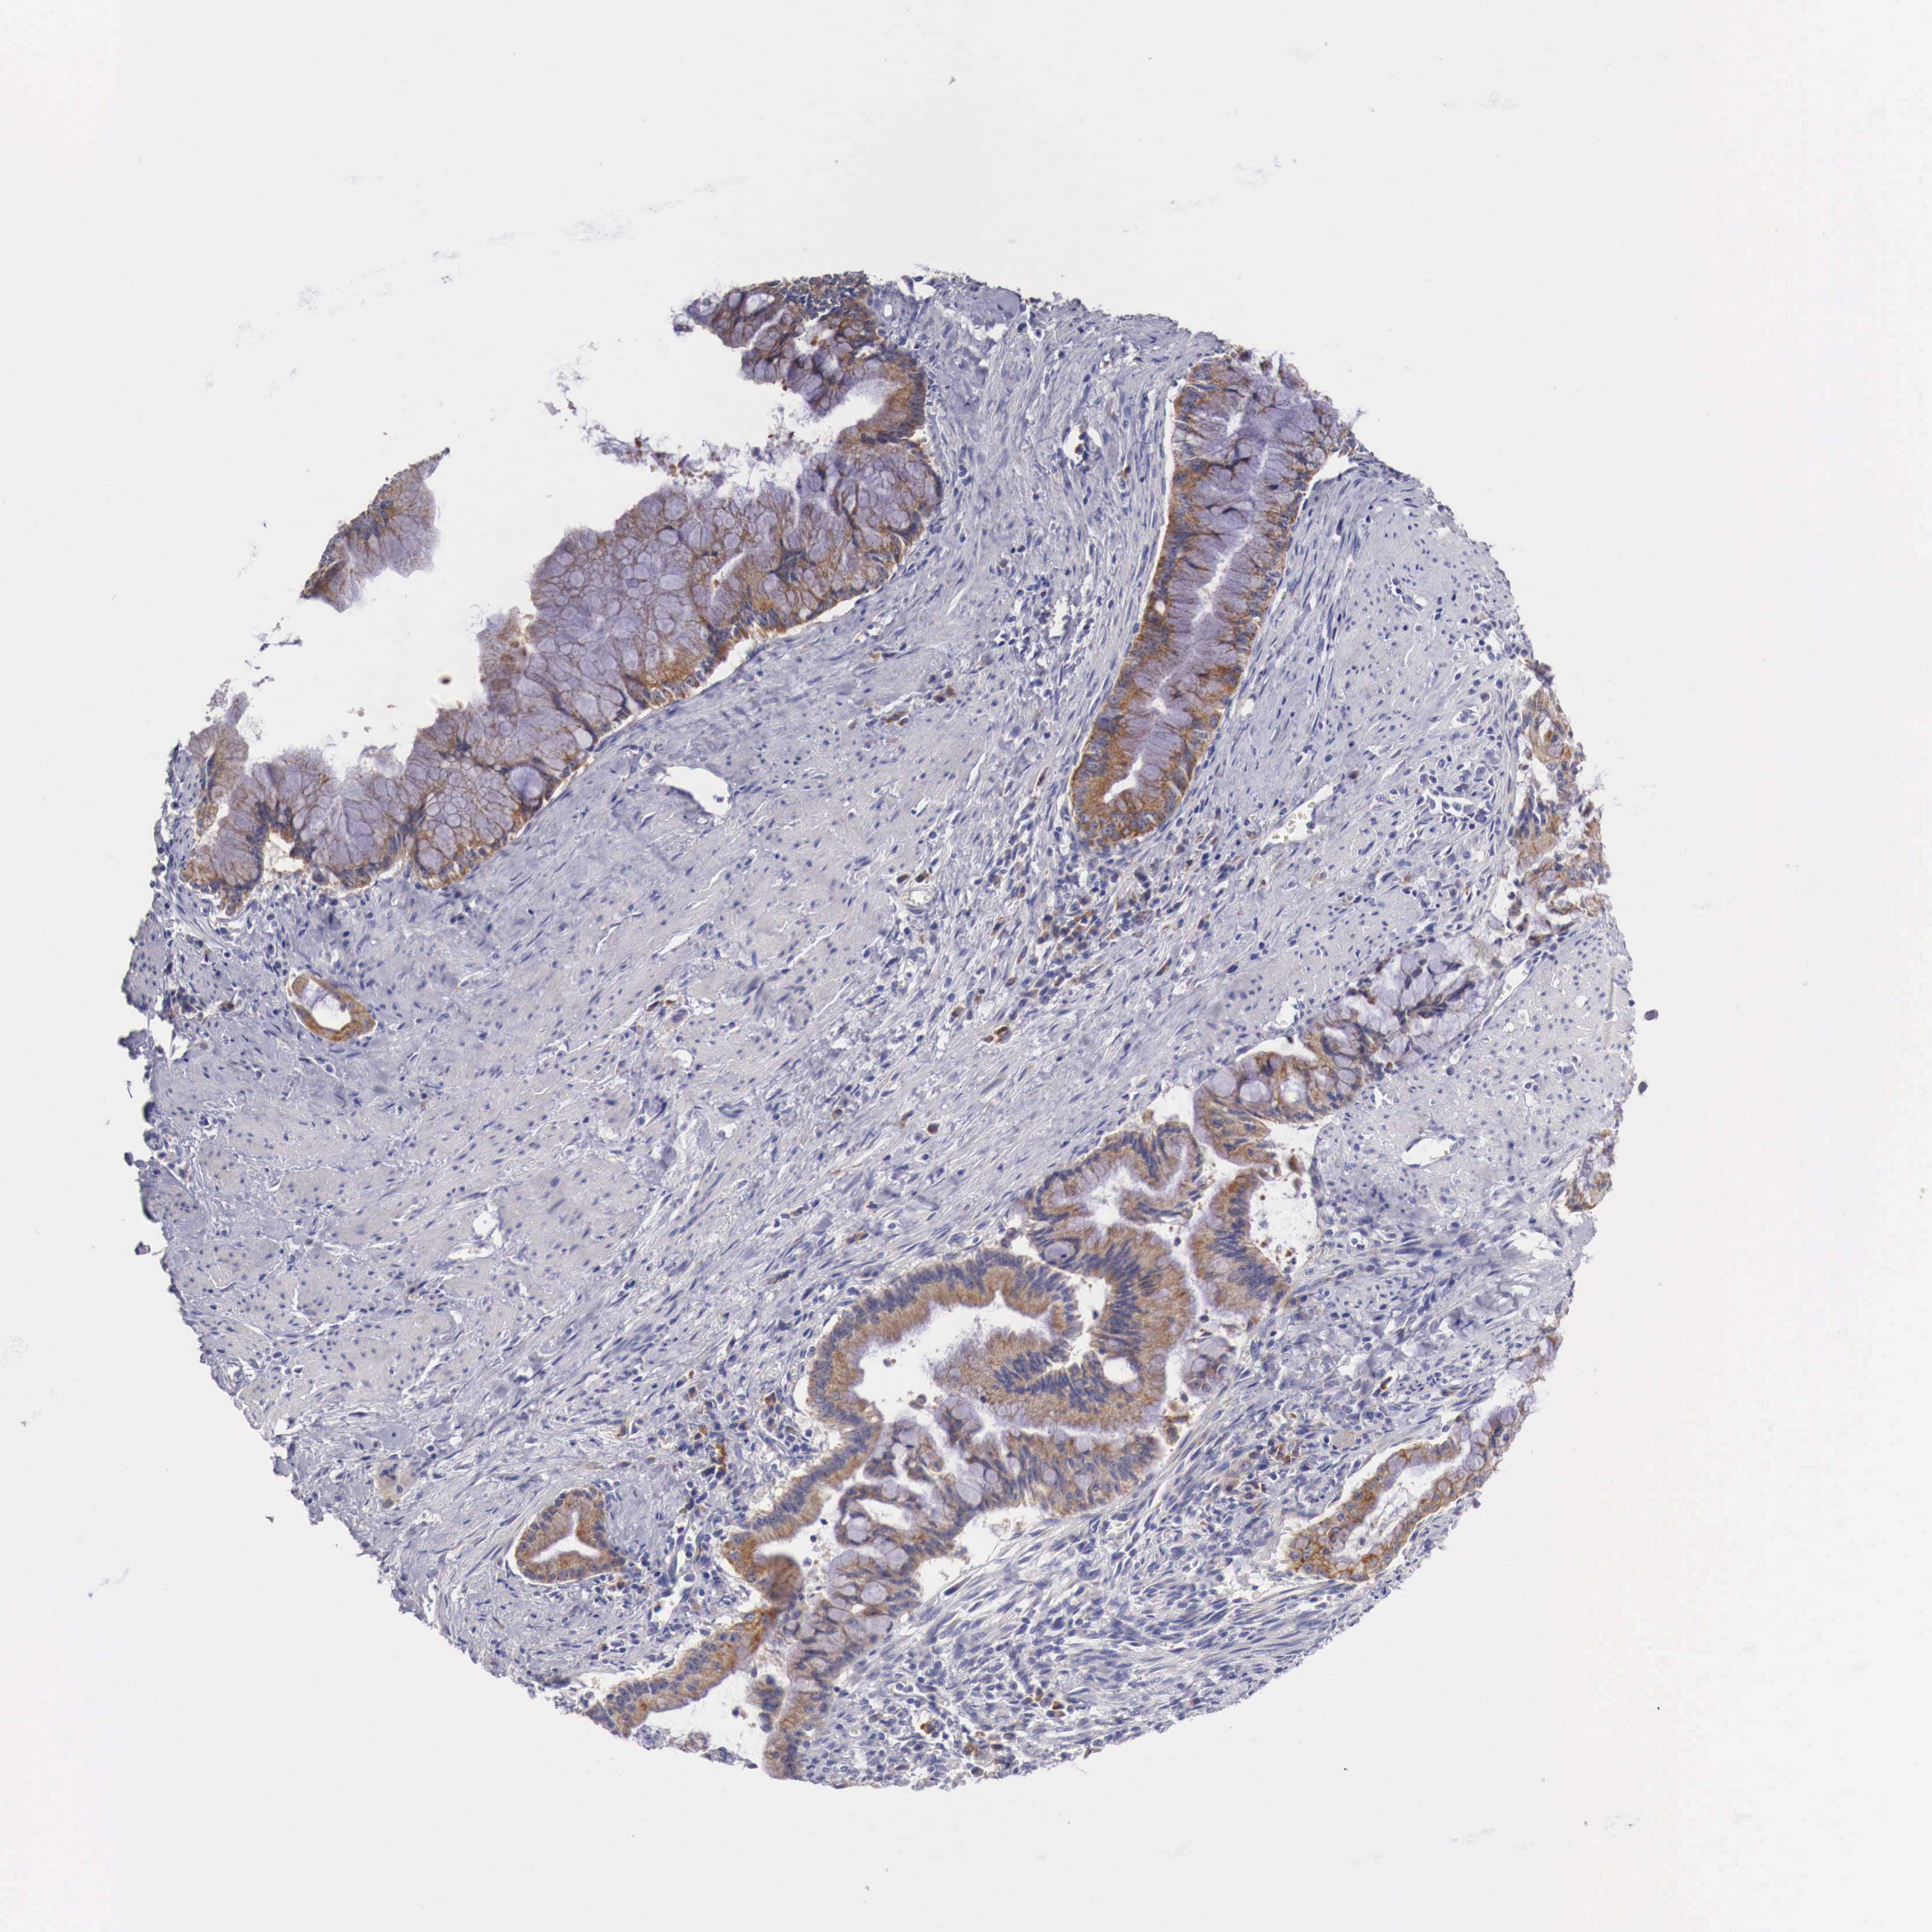

PANCREATIC CANCER - Protein expressioni

A mouse-over function shows sample information and annotation data. Click on an image to view it in a full screen mode. Samples can be filtered based on level of antibody staining by selecting one or several of the following categories: high, medium, low and not detected. The assay and annotation is described here.

Note that samples used for immunohistochemistry by the Human Protein Atlas do not correspond to samples in the TCGA dataset.

Antibody stainingi

Antibody staining in the annotated cell types in the current human tissue is reported as not detected, low, medium, or high, based on conventional immunohistochemistry profiling in selected tissues. This score is based on the combination of the staining intensity and fraction of stained cells.

Each image is clickable and will lead to virtual microscopy that enables deeper exploration of all samples and also displays staining intensity scores, fraction scores and subcellular localization as well as patient and tissue information for each sample.

Antibody HPA000545

Staining

High

Medium

Low

Not detected

Intensity

Strong

Moderate

Weak

Negative

Quantity

>75%

75%-25%

<25%

None

Location

Nuclear

Cytoplasmic/membranous

Cytoplasmic/membranous,nuclear

Adenocarcinoma, NOS